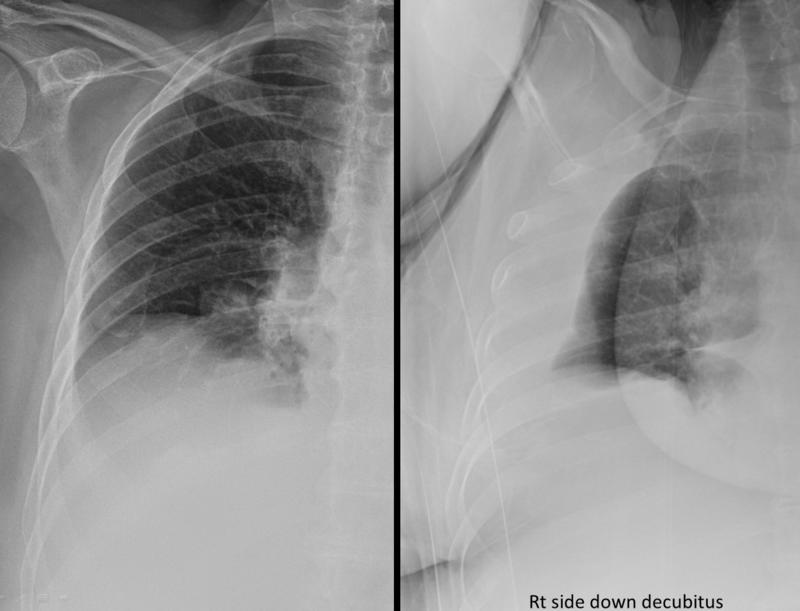

Subpulmonic effusion